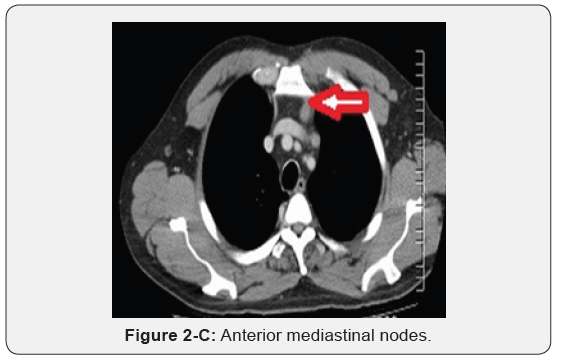

Immunohistochemistry revealed a strong positivity for AE1/ AE3 and Cytokeratin 20 (CK20), and PASD stained for mucin, but the staining for Cytokeratin 7 (CK7), p63, and TTF-1 was negative. The findings suggested a likely primary colorectal origin. He underwent an urgent OGD and full colonoscopy. OGD revealed a normal esophageal mucosa and mild gastritis which tested negative for H. pylori. Full colonoscopy detected a partially-obstructing circumferential mass at the proximal transverse colon near the hepatic flexure. The biopsy report from this colonic mass confirmed an invasive poorly-differentiated colonic adenocarcinoma and the findings were almost identical to the left supraclavicular node’s biopsy. The patient had a computed tomography (CT) scan of the chest, abdomen and pelvis which depicted a locally advanced proximal transverse colon tumor spreading well beyond the serosa posteriorly with local infiltration of pericolic fat and regional lymphadenopathy Figure 2-A. There was a significant metastasis in the para-aortic nodes Figure 2-B, anterior mediastinal nodes Figure 2-C and left supraclavicular nodes Figure 2-D. No evidence of hepatic, pulmonary or bony metastasis noted. Carcinoembryonic antigen (CEA) level was above the normal (22 ng/ml, normal reference <3.5 ng/ml). Alpha-fetoprotein (AFP) level was within the normal ranges.

Distal metastasis of colorectal tumors to mediastinal lymph nodes without lung metastasis is an exceedingly rare entity [5,12- 15]. In fact, Kousa et al. mentioned only 7 cases of metachronous mediastinal lymph node metastasis from colorectal cancers in the English literature, including his reported one [15]. Nevertheless, the exact route of mediastinal lymph node metastasis with colon cancers is not yet known [5,13,15]. It has been postulated that involvement of the mediastinal lymph nodes is through the para-aortic lymphatic drainage route towards the thoracic duct [13]. This presumed theory might explain the metastasis to the posterior mediastinal nodes group due to their close proximity to (and their eventual drainage) to the thoracic duct, but would not justify the involvement of the anterior mediastinal lymph nodes group (as occurred in our patient), which are however, well-distant from the thoracic duct and they don’t usually drain to it as there is no direct communication between the thoracic duct and Broncho mediastinal trunk that drain these lymph nodes group [15].

Nevertheless, MacLoud et al. [16] suggested a retrograde reflux of tumor micro-emboli from the thoracic duct into the Broncho mediastinal trunk through incompetent lymphatics valves and this would possibly explain the anterior mediastinal lymph nodes involvement. Cervical and left supraclavicular lymphadenopathy is well-known to be the first manifestation of colorectal tumors [6,7]. Nevertheless, the occurrence of distant cervical and supraclavicular nodes metastasis without solid organs metastasis is typically rare and was reported only in a few cases in the reviewed literature [6-9]. It has been suggested that after the metastatic involvement of para-aortic lymph nodes, a sequential left supraclavicular metastasis occurs as a result of infiltration of the thoracic duct with tumor cells with formation of skip metastasis between the regional lymph node stations and the distal nodes which are considered as end-nodes of the lymphatic pathway [6].